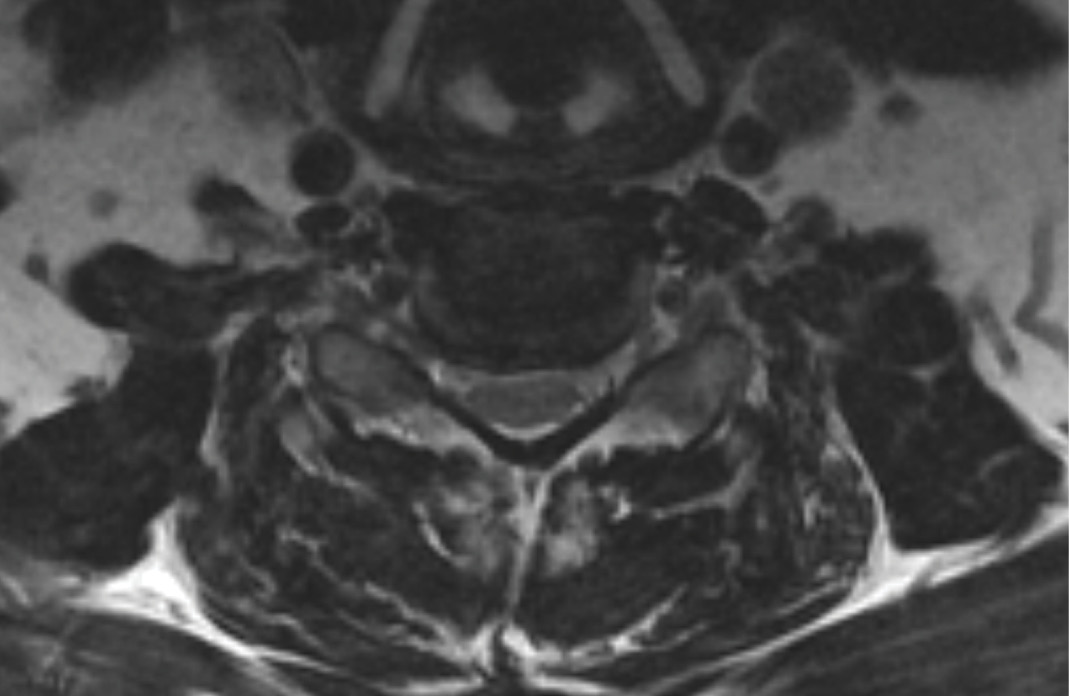

MRIs illustrated mild degenerative disc disease from C4-6 with disc herniations at both C4-5 and C5-6. The axial slice through C4-5 showed a right central disc herniation causing central and mainly right-sided foraminal stenosis. The axial slice through C5-6 showed a central disc herniation also causing central and mainly right-sided foraminal stenosis. The axial slice through C6-7 showed a left-sided disc herniation causing some left-sided foraminal stenosis, however, the patient did not demonstrate any left-sided symptoms.

During the procedure, prodisc C Vivo fit well within the C4-5 concave endplate. I expected to use a flat endplate prodisc C SK at C5-6, however I trialed the domed prodisc C Vivo and it actually looked good, so I unexpectedly used matching implants.

In future cases, I expect to use prodisc C Vivo to match the concavity with non-degenerated levels, and prodisc C SK for more degenerated levels, where flatter endplates may be needed. It is very useful to have a system that can adapt to the degenerated anatomy as needed.